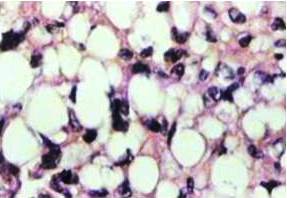

Estudio histopatológico e inmunohistoquimico de pulmón derecho: secciones de biopsias de neoplasia de aspecto mesenquimal, constituida en áreas por células fusiformes, con escaso citoplasma con núcleos periféricos con ligero pleomorfismo e hipercromatismo, identados, con citoplasma con vacuolas de aspecto lipomatoso, células estrelladas escasa mitosis atípica inmersos en matriz mixoide. Con escasos lipoblastos en “anillo de sello”. Las luces bronquiales se evidencian dilatadas quísticamente ocupadas por material de aspecto proteináceo. El resto de pulmón no tumoral muestras extensas áreas de atelectasia. Desde el punto de vista inmunohistoquimico las células neoplásicas resultaron positivas para vimentina (3+), S-100 (2+) negativas.

Estudio histopatológico e inmunohistoquimico de pulmón derecho: secciones de biopsias de neoplasia de aspecto mesenquimal, constituida en áreas por células fusiformes, con escaso citoplasma con núcleos periféricos con ligero pleomorfismo e hipercromatismo, identados, con citoplasma con vacuolas de aspecto lipomatoso, célula estrellada escasa mitosis atípica inmersos en matriz mixoide. Con escasos lipoblastos en “anillo de sello”. Las luces bronquiales se evidencian dilatadas quísticamente ocupadas por material de aspecto proteináceo. El resto de pulmón no tumoral muestras extensas áreas de atelectasia. Desde el punto de vista inmunohistoquimico las células neoplásicas resultaron positivas para vimentina (3+), S-100 (2+) negativas para CD-34. Hallazgos histopatológicos e inmunohistoquimicos compatibles con el diagnóstico de liposarcoma mixoide primario de pulmón de bajo grado de malignidad (Figura 5).